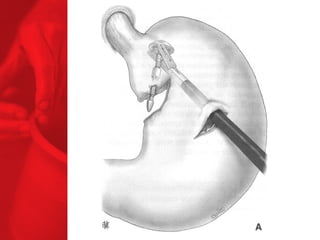

ANNEAU GASTRIQUE AJUSTABLEProcédure restrictive SAGB ® (anneau gastrique ajustable suédois) forme d'un sablier l'opération inverse peut être effectuée la digestion et l'absorption sont normales, aucun effets secondaires de la malabsorption moyenne de surcharge pondérale à 3, 4 et 5 ans après l'étude : 49, 55 et 57% respectivement* diminue le diabète de type 2 chez près de 77% des patients** *Laparoscopic SAGB: a 5-year Prospective Study, R. Steffen et al, Obesity Surgery, 13, 2003, 404-411 **Buchwald H, Avidor Y, Braunwald E, et al. Bariatric Surgery—A Systematic Review of the Literature and Meta-analysis. Journal of the American Medical Association 2004 Oct 13;292(14).

COMMENT FONCTIONNE L'ANNEAUGASTRIQUE AJUSTABLE ? Facteurs chirurgicaux Restriction du volume des repas Un sentiment de satiété plus tôt et pendant plus longtemps Restriction plus haute ou plus basse grâce au règlage de l'anneau Facteurs pour les patients Apport en calories voué à l'échec par une mauvaise nourriture et mauvais liquides dépense en calories BILAN ENERGETIQUE = apport alimentaire dépense en énergie